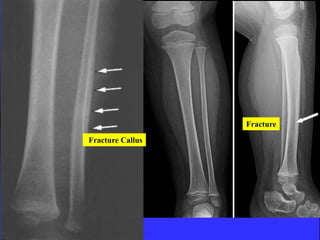

Fracture

Fracture Callus

Stress fracture

Callus due to Fracture